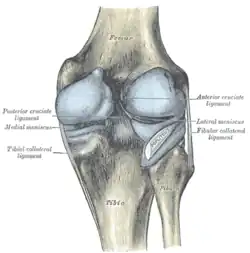

Zentrale Bandsicherung

Die Kreuzbänder (Ligamenta cruciata) ziehen von der Grube zwischen den Oberschenkelknorren zum Schienbein. Von der Seite und von vorn betrachtet überkreuzen sie sich dabei in ihrem Verlauf.

Indem die Kreuzbänder ein verschobenes Abgleiten der Gelenkflächen nach vorn oder hinten (Translation) verhindern, stabilisieren sie das Knie. Zusätzlich hemmen sie die Drehbewegung, vor allem die Einwärtsdrehung, bei der sie sich umeinander wickeln und das vordere Kreuzband sich spannt. Bei der Auswärtsdrehung wickeln sie sich auseinander, wodurch das Knie bei maximaler Streckung immer ein wenig nach außen gedreht wird (Schlussrotation). Die klassische Verletzung des vorderen Kreuzbandes tritt daher, z. B. beim Skifahren, bei gebeugtem Knie und Einwärtsdrehung unter Gewalteinwirkung auf.

Eine Besonderheit ergibt sich durch die Lage der Kreuzbänder zur Gelenkkapsel. Sie liegen zwar innerhalb der äußeren Schicht der Gelenkkapsel (intrakapsulär), jedoch außerhalb der Innenhaut. Diese spart die Kreuzbänder nach hinten offen scharf U-förmig aus. Somit liegen sie außerhalb der eigentlichen Gelenkhöhle (extraartikulär). Diese Tatsache lässt sich entwicklungsgeschichtlich dadurch erklären, dass die Kreuzbänder während der Evolution von hinten eingewandert sind und dabei die Kapsel-Innenhaut mit nach vorne geschoben haben.

Vorderes Kreuzband

Das vordere Kreuzband (Ligamentum cruciatum anterius – bei Tieren Ligamentum cruciatum craniale) zieht von der vorderen Einmuldung zwischen den Schienbeinknorren zur Seite und etwas nach hinten, um an der Innenseite des seitlichen Oberschenkelknochens anzusetzen. Dabei teilt es sich in ein vorne-mittiges und in ein hinten-seitliches Bündel auf. Durch die weite Fächerung der Ursprungsfläche dieser Bündel ist sowohl bei Beugung, als auch bei Streckung ein Teil des vorderen Kreuzbandes gespannt. Dadurch verhindert es bei ausgestrecktem Bein eine Überstreckung (Hyperextension), während es bei Beugung dem Vorschub des Schienbeines entgegenwirkt („vordere Schublade“).

Hinteres Kreuzband

Das hintere Kreuzband (Ligamentum cruciatum posterius – bei Tieren Ligamentum cruciatum caudale) ist kräftiger und hat seinen Ursprung in der hinteren Einmuldung des Schienbeinplateaus und zieht nach vorne-mittig, um an der seitlichen Vorderfläche des inneren Oberschenkelknochens anzusetzen. Es spannt sich bei Beugung und verhindert damit ein nach hinten gerichtetes Weggleiten des Schienbeines (hintere Schublade). Bei ausgestrecktem Bein unterstützt das hintere Kreuzband das vordere beim Vorbeugen einer Überstreckung. Seine Hauptaufgabe ist jedoch die Stabilisierung des Knies bei Beugung und unter Last.

Menisken

Da die miteinander in Verbindung stehenden (artikulierenden) Gelenkflächen nicht genau aufeinander passen, wird diese „Ungleichheit“ (Inkongruenz) durch halbmondförmige Faserknorpelscheiben, die Menisken ausgeglichen, die den Drehbewegungen folgen können. Eine weitere Aufgabe der Menisken besteht in der Vergrößerung der Kontaktfläche zwischen Schienbein und Oberschenkelknochen.

Man unterscheidet einen Innenmeniskus (Meniscus medialis), der C-förmig, größer und etwas unbeweglicher (da mit dem Innenband verwachsen) ist, und einen Außenmeniskus (Meniscus lateralis), der kreisförmig, kleiner und beweglicher ist (da er mit keinem Seitenband verwachsen ist). Die Menisken sind im Querschnitt keilförmig. Die hohe Kante liegt außen, die niedrige innen. Da die Oberschenkelknochen genau in der Mitte direkt auf dem Schienbeinplateau und peripher auf den Menisken aufliegen, tragen diese einen wesentlichen Teil der Last.